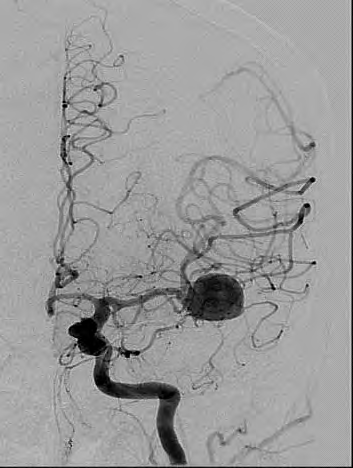

Świadczenie usług medycznych …

Które badanie zostało zarejestrowane na przedstawionym radiogramie?

Ilustracja do pytania 31

A. Dróg żółciowych metodą cholangiografii śródoperacyjnej.

B. Płuc wykonane metodą Przybylskiego.

C. Jamy brzusznej wykonane poziomą wiązką promieniowania.

D. Układu moczowego z użyciem środka kontrastującego.